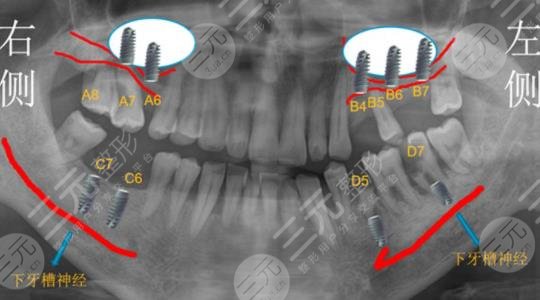

一次在户外骑车的时候出现了牙齿的脱落,右侧总共去了5颗牙,牙齿缺失之后只能到医院做牙齿种植治疗。牙齿种水的价格略贵,到医院检查之后医生说可以分两次进行,第1次种植两颗,过了几个月之后再种植剩下的两颗。

我选择的是一款进口的牙体,材料价格是中等的。在去医院的路上我还是很紧张的,因为第一次去做这也的手术,但是在牙齿种植的过程当中,医生先是打了局麻药物,手法也十分温柔,然后就开始进行操作,主要是将牙槽骨断开一个洞,然后再将假牙放里面。牙齿种植之后和自己的真牙并没有什么两样,较为的结实,平时吃一些坚硬的食物也是可以的。由于进行了两次的治疗,总共下来接近有一年的时间。牙齿痛的价格真的还挺贵的,所以平时一定要爱护自己的牙齿。不得不说浙江大学医学院附属口腔医院技术还是很过关的。下面我就把价目表放在下面了,供大家参考一下。